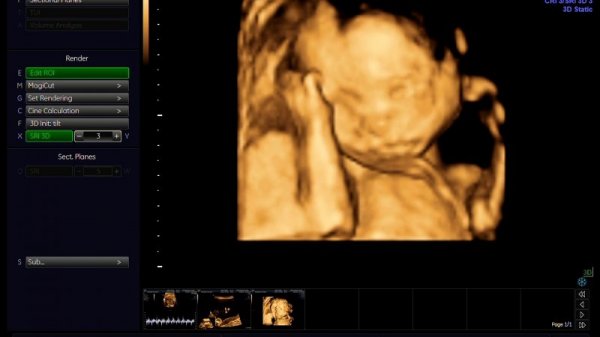

4. Đi khám và siêu âm thai lần 4 (22 tuần – 28 tuần): Theo dõi sự phát triển bất thường của thai nhi

Các giai đoạn siêu âm thai giúp mẹ theo dõi sự phát triển bất thường của thai nhi và có hướng xử lý kịp thời. (Ảnh: benhvienthucuc.vn)

• Khám thai và tư vấn.

• Để đánh giá hình thái của thai nhi thì lúc này mẹ cần siêu âm 4D.

• Siêu âm để có thể đánh giá độ dài của cổ tử cung, nhằm phòng ngừa trường hợp nguy cơ sinh non.